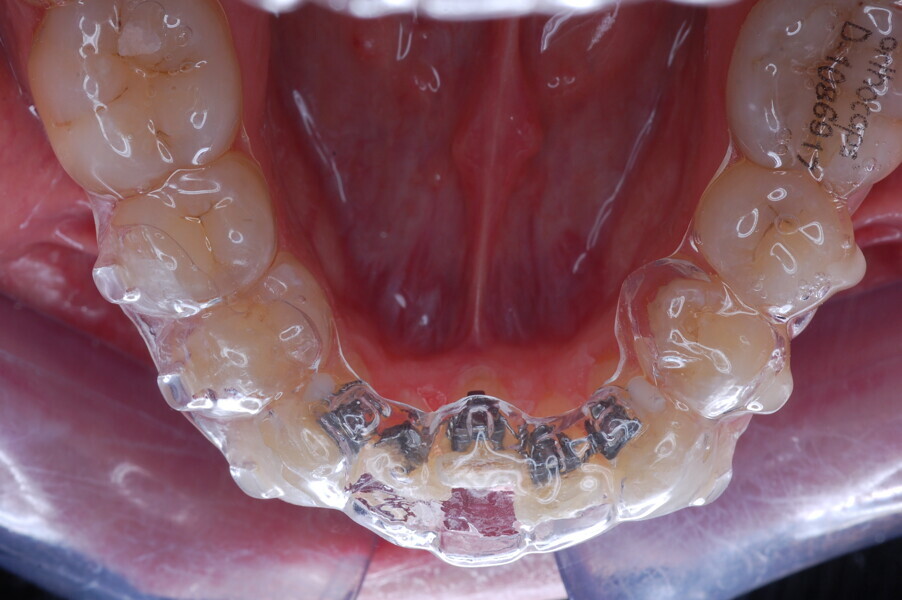

Fig. 25–28: Clinical progress after 12 months of aligner treatment.

Fig. 30: Indirect bonding tray and 0.014 in. nickel–titanium wire.

Fig. 31: Lingual bracket placement.

After 12 months of aligner use (Figs. 25–29), we finally had space for the fixed sectional lingual appliance that we had planned. As described, we asked for an orthocaps HAT, a new concept based on the idea of using fixed auxiliary modules (brackets, bands, wires and expansion or anchorage appliances) simultaneously with aligners to achieve a more effective treatment for better clinical results. The exact times, modalities and use of such auxiliaries can be determined in the treatment plan. The method makes it possible to carry out the bulk of the movement with aligners while using auxiliaries as needed primarily to support and enable complex movement. For the treatment phase in which a partial lingual appliance was used in this patient, an indirect bonding tray to bond the lingual auxiliary was fabricated by Ortho Caps and sent to us for bonding the brackets.

CAD/CAM method for fabricating the HAT lingual auxiliary

The final positions of the mandibular anterior teeth were simulated in the CAD treatment planning software. After moving of the teeth to their final positions, virtual brackets were placed at appropriate positions on the final set-up in the CAD software. These positions allow a virtual straight, rectangular lingual wire to pass passively through the bracket slots without colliding with the brackets. In the next step, the teeth with their respective brackets were moved back to their original positions. 3D printing was used to print the final moulds with brackets, on which a silicone transfer tray could then be formed. Lingual brackets (JOY lingual brackets, Adenta) were then placed into the silicone transfer tray to be sent to us for indirect bonding together with a 0.014 in. nickel–titanium lingual archwire (Figs. 30 & 31).